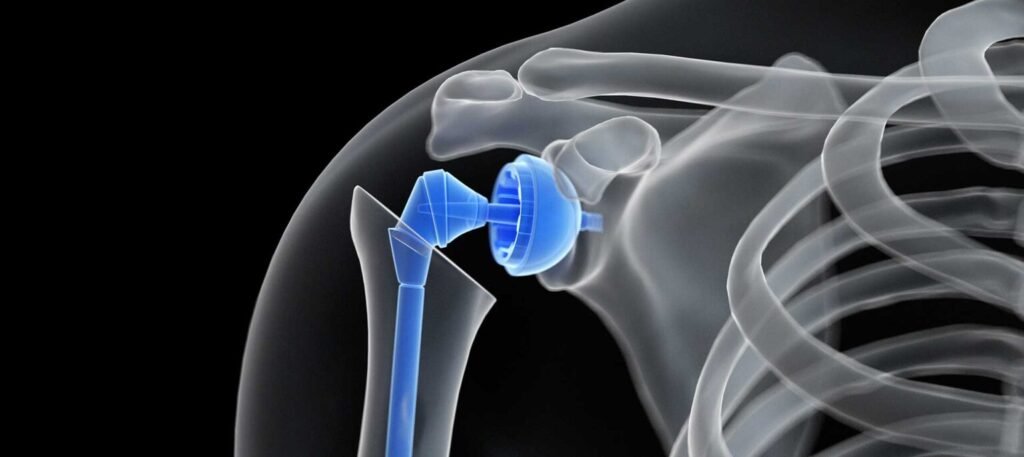

Omuzda sıklıkla görülen impingement (sıkışma hastalığı), zaman içerisinde kas yırtılmaları ve buna bağlı eklemin bozulmasına yol açabilir. Yaş olarak 60-70 yaş aralığında gelişen bir hastalıktır. Omuz protezi, rotator manşet artropatisi olarak adlandırılan bu eklem bozulmasında kullanılır. Bu durumda omuzdaki kasların büyük kısmı geniş kronik yırtıklar nedeniyle bozulmuş ve eklem kıkırdağı iyi durumda değildir. Çözüm olarak reverse (ters tipte) omuz protezi uygulanır. Biomekanik olarak deltoid kası ve subskapularis kasının sağlam bölümleri sayesinde omuza tekrar hareket kabiliyetini kazandırmak amaçlanır. Omuz eklem protezleri eklemin onarılamayacak kırıkları sonrasında ya da eklemin yıpranması sonrası da konulabilmektedir. Ekleme ait çok parçalı kırıklar, kırıklı çıkıklar plak vida sistemleri ile tedavi edilemeyecek durumda olduğunda protez ile eklemin yeniden oluşturulması gerekebilir. Bu durumda kırık sonrası kemik stokunun korunmasına yönelik protezler kullanılır. Kırık genellikle osteoporotik zeminde oluştuğu için genellikle omuz protezleri çimentolu tercih edilir. Tüm omuz protez ameliyatlarında başarıyı etkileyen temel faktörlerin başında; protez yüksekliği, başın şeklinin çıkarılan anatomik baş ile aynı olması ve en önemlisi başa yapışan kasların tekrar protez üzerinde etkili tutturulması yer alır. Bu kaslar kemiksel yapışma yerleriyle birlikte, kalın dikiş materyalleri sayesinde protez çevresine dikilmektedir. Kırık sonrası protezlerde, tuberkül olarak adlandırılan bu kısımların, ameliyat sonrası protez ile bütünleşmesi, protezin kolu kaldırabilecek güce kavuşması için önemlidir. Bu nedenle omuz protezi sonrası rehabilitasyon programı ve doktorunuzun önerilerine sıkı sıkıya uymanız gerekmektedir. Omuz protezleri sonrası 4-6 haftada fizik tedavi değişik evrelerden geçmektedir.